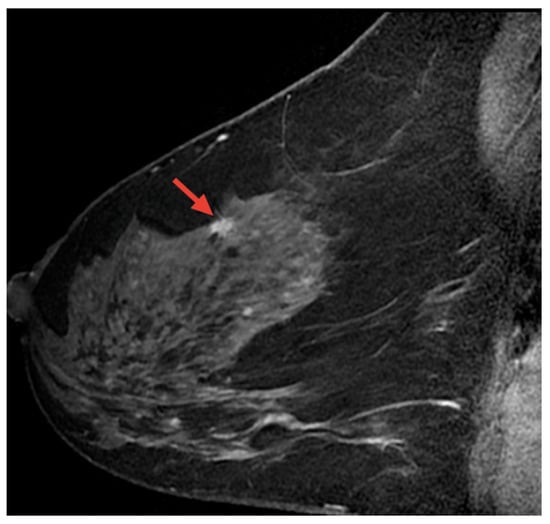

8.3. Breast Cancer Detection Based on Magnetic Resonance Imaging (MRI) Images

- Berg, W. Breast MRI|DenseBreast-info, Inc.—densebreast-info.org. Available online: https://densebreast-info.org/screening-technologies/breast-mri/ (accessed on 1 December 2024).